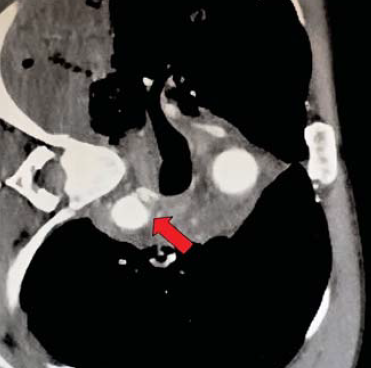

6. ábra.

7. sorszámú betegünk CTA vizsgálata multiplex gerinc, borda és jobb oldali acetabulum törés mellett kialkult isthmicus aorta intima sérülését mutatja.

7. 32 éves férfi autóbaleset okozta koponyaűri és arcüregi vérzéssel, agyödémával, kétoldali pleuralis és mediastinalis folyadékgyülemmel, PTX és hasi szabad levegővel, máj és lép körüli kevés véres folyadékkal, felső thoracalis és lumbalis csigolya és jobb lapockatöréssel, jo. acetabulum töréssel, femur luxatioval, kiterjedt mellkas és hasfali subcutan emphysemával, intubálva eszméletlen állapotban került felvételre. Neurologiai statusának rendeződése, mellkasi sérüléseinek ellátása és fracturáinak műtéti rögzítése után, 16 nappal a sérülés követően, a. subclavia transpositiot elvégezve, isthmicus stentgraft beültetés történt. A bal lapockatörés után kialakult dorsalis septicus haematomája 2 hónapos kezelés után gyógyult (6.,7.,8. ábra).

7. ábra.

Előző ábrán bemutatott intima sérülés localis expandáló álaneurysma képződéshez vezetet.